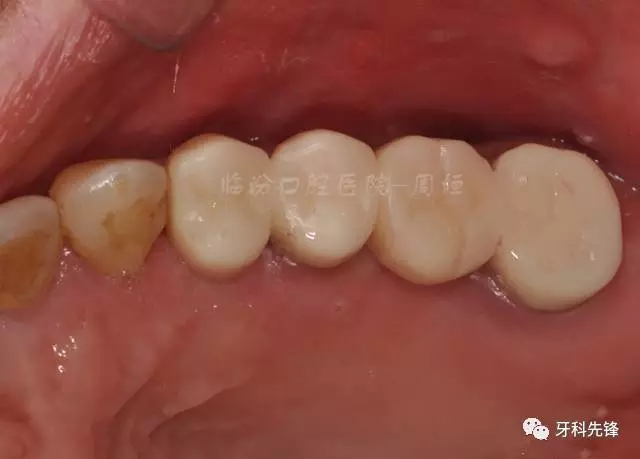

圖30術后頜面照

640.webp (34).jpg